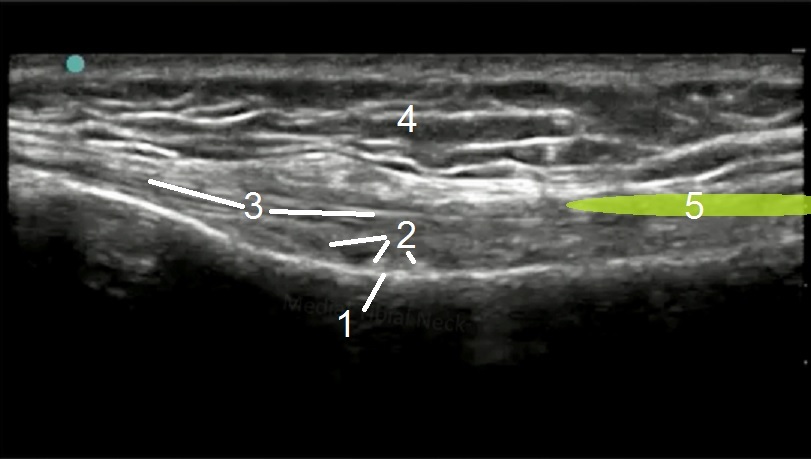

膝部鹅足解剖结构 1 图像

内侧胫骨颈

内侧关节血管

内侧副韧带 (MCL)

皮下脂肪

倾斜鹅足